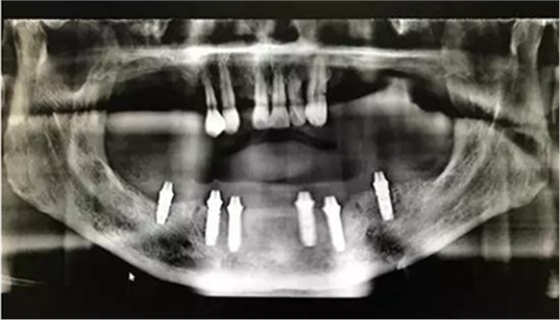

從CT可以看出患者前牙區(qū)牙槽骨非常薄,有的地方3.5mm不到,左側(cè)4號牙位有嚴(yán)重的骨吸收,需要進(jìn)行植骨,后牙區(qū)離神經(jīng)管較近,設(shè)計種植短粗型種植體。

通過術(shù)前精確的設(shè)計,避開了患者骨壁較薄需要做骨劈開的區(qū)域,避免了大翻瓣造成較大創(chuàng)傷,大大提高了患者的舒適度。

全程手術(shù)采用小翻瓣微創(chuàng)種植,選擇初期穩(wěn)定性較好的植體進(jìn)行即刻負(fù)重。整個手術(shù)從開始到最終戴上臨時牙,只花費2個小時的時間,就讓患者恢復(fù)了完美笑容。數(shù)字化種植為醫(yī)生和患者帶來不一樣的感受!